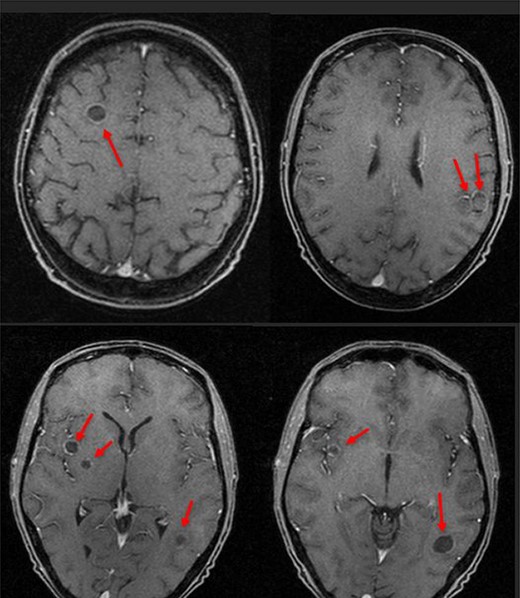

Six days following his initial follow-up, this patient was brought to the emergency department by ambulance following a witnessed seizure. He was distressed and confused on arrival but otherwise apyrexial with a non-tender abdomen. Initial blood tests were as follows: haemoglobin 82 g/l, WCC 25.3 × 109/l, CRP 284 mg/l, Plts 477 × 109/l, Neuts 23.8 × 109/l, Lymph 0.6 × 109/l, bilirubin 30 μmol/l, albumin 266 g/l, ALT 133 IU/l and alkaline phosphatase 914 IU. All other blood tests were non-contributory. Blood cultures isolated a Streptococcus intermedius bacteraemia. CT revealed four large hepatic abscesses with the largest in segment 4b measuring 92 × 90 mm and a right hepatic vein thrombus. Three of the liver abscesses were drained to completeness by interventional radiology (IR). Magnetic resonance imaging (MRI) showed several focal restricting intraparenchymal brain lesions, posterior left temporal lobe measuring 1.7 cm and multiple smaller lesions within the right frontal, right para-ganglionic region, right parahippocampal, left uncal regions, right cerebellar hemisphere and left pons (Figs 1 and 2) consistent with brain abscesses.

An MRI head then showed that the intra-cerebral cavitating lesions were solidifying and reducing in size. There were also several new microabscesses present in the left temporoparietal region. A further 5-week intraveneous (IV) antibiotic therapy solidified the new lesions.